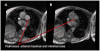

Pulmonary hypertension is a condition of varied etiology, commonly associated with poor clinical outcome. Patients are categorized on the basis of pathophysiological, clinical, radiologic, and therapeutic similarities. Pulmonary arterial hypertension (PAH) is often diagnosed late in its disease course, with outcome dependent on etiology, disease severity, and response to treatment. Recent advances in quantitative magnetic resonance imaging (MRI) allow for better initial characterization and measurement of the morphologic and flow-related changes that accompany the response of the heart-lung axis to prolonged elevation of pulmonary arterial pressure and resistance and provide a reproducible, comprehensive, and noninvasive means of assessing the course of the disease and response to treatment. Typical features of PAH occur primarily as a result of increased pulmonary vascular resistance and the resultant increased right ventricular (RV) afterload. Several MRI-derived diagnostic markers have emerged, such as ventricular mass index, interventricular septal configuration, and average pulmonary artery velocity, with diagnostic accuracy similar to that of Doppler echocardiography. Furthermore, prognostic markers have been identified with independent predictive value for identification of treatment failure. Such markers include large RV end-diastolic volume index, low left ventricular end-diastolic volume index, low RV ejection fraction, and relative area change of the pulmonary trunk. MRI is ideally suited for longitudinal follow-up of patients with PAH because of its noninvasive nature and high reproducibility and is advantageous over other biomarkers in the study of PAH because of its sensitivity to change in morphologic, functional, and flow-related parameters. Further study on the role of MRI image based biomarkers in the clinical environment is warranted.